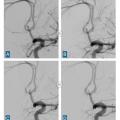

L’angiographie digitale permet de planifier et de suivre le traitement lorsqu’il est réalisé par voie endovasculaire. (fig. 4)